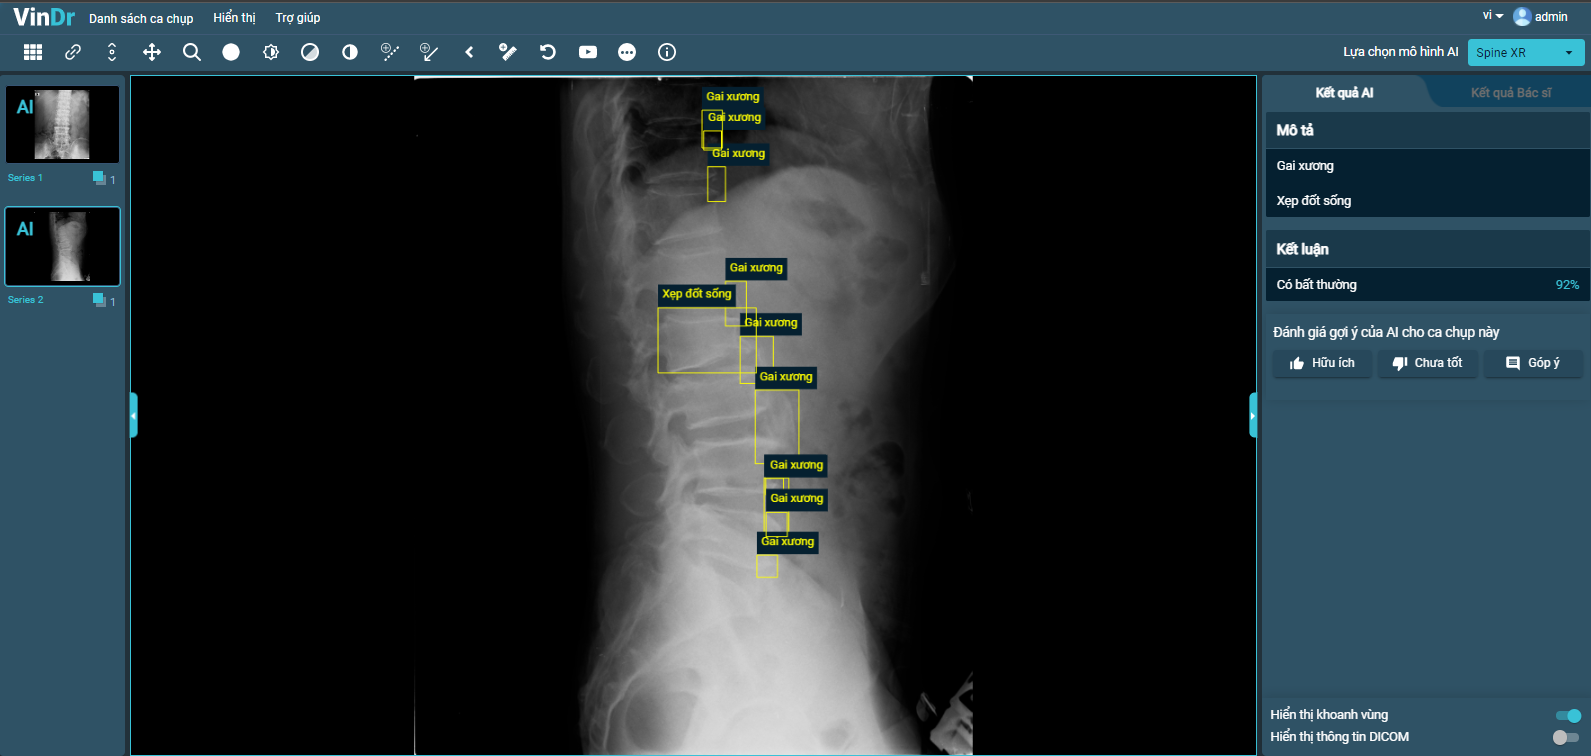

VinBigdata phát triển tính năng chẩn đoán X-quang cột sống trên VinDr.

Sau hơn một năm tiếp tục nghiên cứu, VinBigdata phát triển tính năng chẩn đoán X-quang cột sống giúp phát hiện sáu loại tổn thương với độ chính xác khoảng 90%, gồm: Gai xương, hẹp khe đĩa đệm, vật liệu phẫu thuật, hẹp lỗ tiếp hợp, trượt đốt sống và xẹp đốt sống.